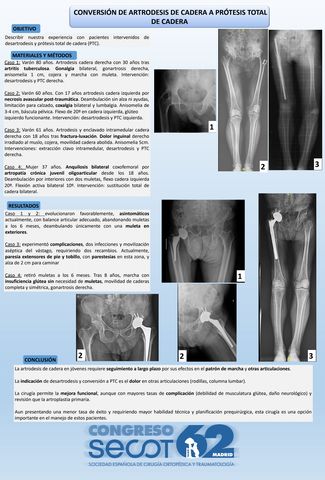

Conversión de Artrodesis de Cadera a Prótesis Total de Cadera.

HENAR MARIA ARQUEROS MARTINEZ, ARIADNA CASADO CASTILLO, DANIEL TORRES RAMOS, DANIEL HORCAJO SANZ, JAVIER MARTINEZ MARTIN